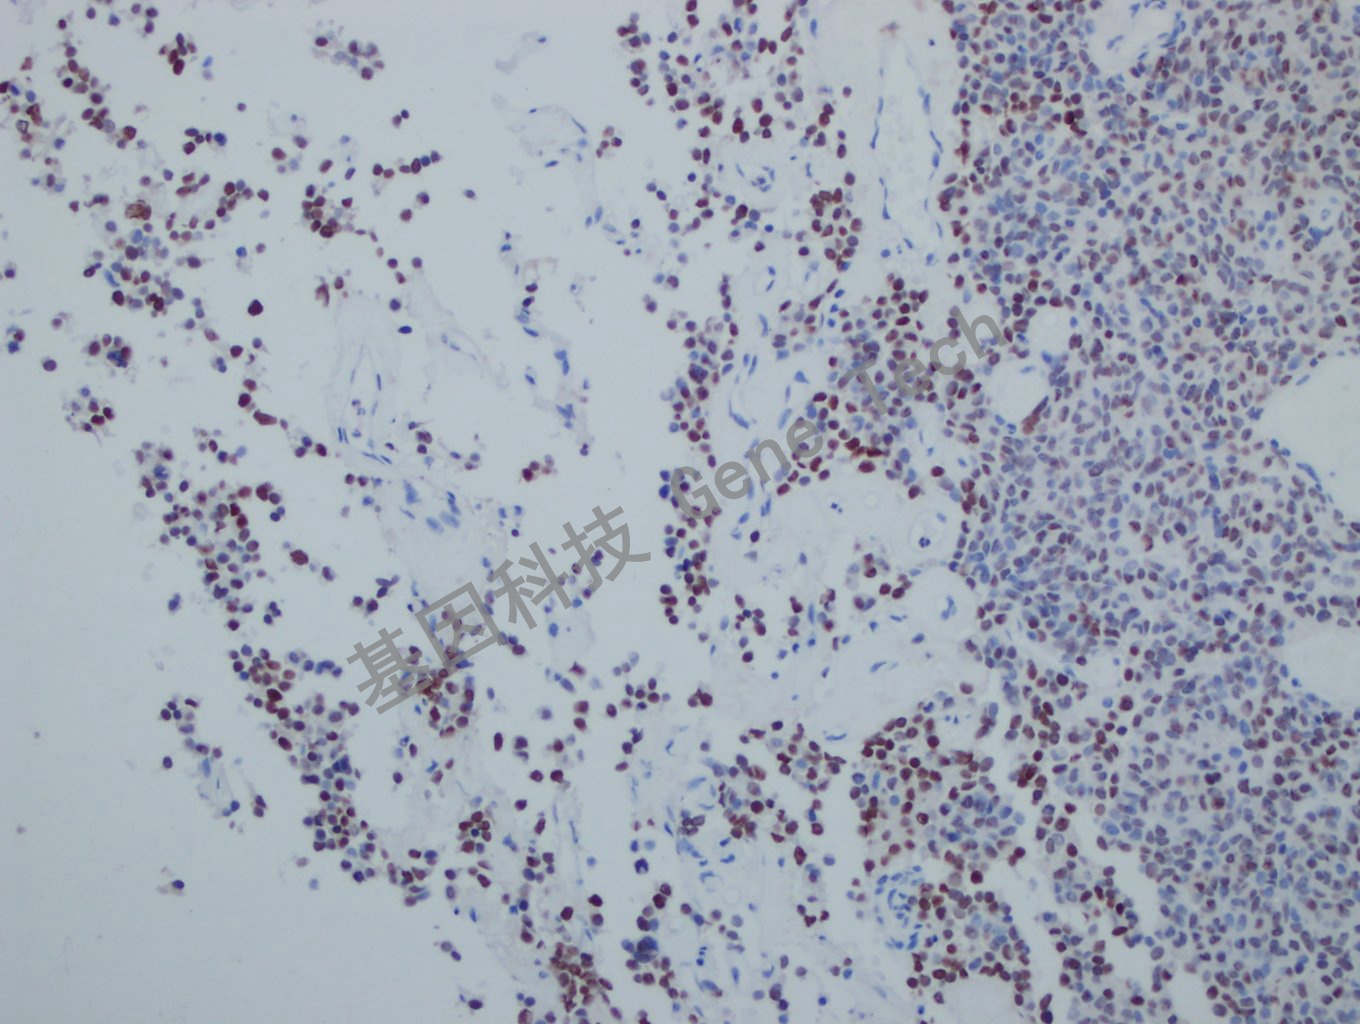

垂体瘤石蜡切片,用 PIT-1(GT2319)染色,细胞核阳性,DAB 显色。